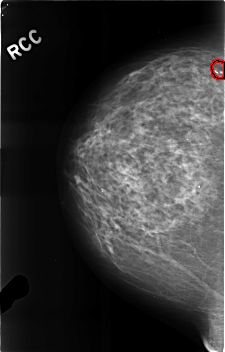

C_0310_1.RIGHT_CC

FILE: C_0310_1.RIGHT_CC.OVERLAY

TOTAL_ABNORMALITIES 1

ABNORMALITY 1

LESION_TYPE CALCIFICATION TYPE PLEOMORPHIC DISTRIBUTION CLUSTERED

ASSESSMENT 3

SUBTLETY 5

PATHOLOGY BENIGN

TOTAL_OUTLINES 1

BOUNDARY